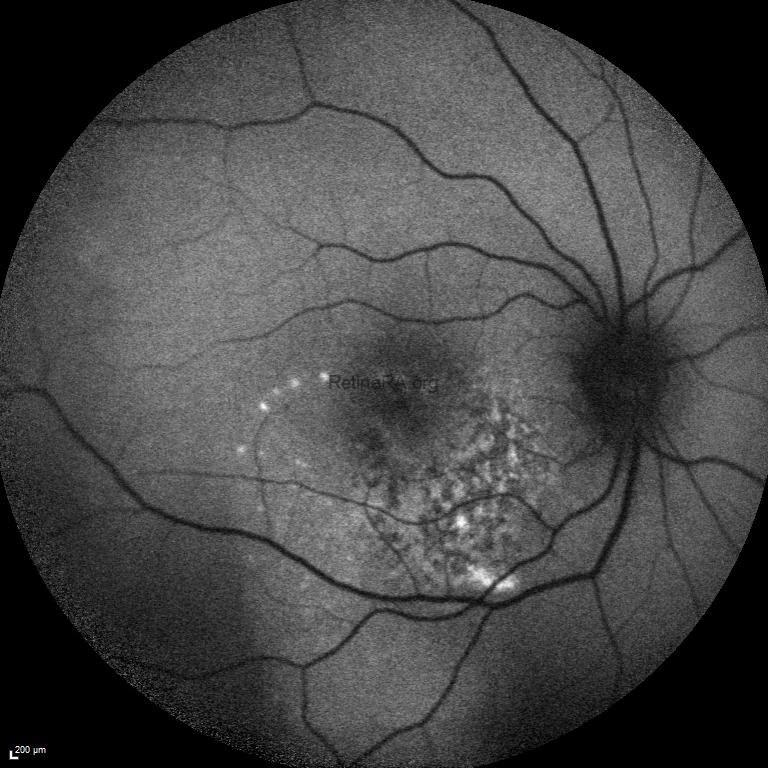

Fundus autofluorescence image demonstrated a mixed autofluorescence pattern. The central area appears hypoautofluorescent, suggestive of decalcification and retinal pigment epithelium atrophy. Surrounding this region, irregular zones of iso- to hyperautofluorescence reflect preserved or calcified segments of the lesion. The mottled autofluorescence is consistent with chronic remodeling of the lesion and may indicate areas at risk for functional deterioration.

Fundus fluorescein angiography showed a mottled pattern of hyper- and hypofluorescence corresponding to the calcified and decalcified portions of the lesion. Early-phase images show background choroidal filling with blocked fluorescence in areas of dense calcification. The central dark ring suggests decalcification and possible RPE atrophy, while focal late hyperfluorescence may represent window defects or early choroidal neovascularization. The lesion borders remain relatively well demarcated throughout the angiographic sequence.